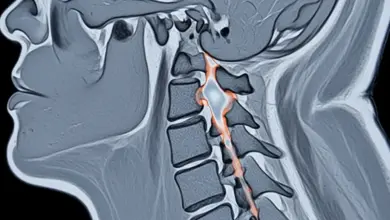

Patologias da Coluna  Mielopatia cervical: como reconhecer e tratarA mielopatia cervical ocorre quando a medula espinhal é comprimida no pescoço, gerando perda de função neurológica, onde identificar cedo… Leia mais »